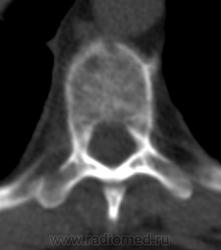

Была взята биопсия с пораженного позвонка, но в материале оказалось мало клеток кости, наличие фиброзных клеток. Материал трепанбиопсии правой подвздошной так же содержал мало клеток, т.к. удалось углубиться всего лишь на 7мм (дальше сломалась игла, по словам врача скорее всего об фиброзное образ.). Можно ли по результатам КТ предложить повторный, более прицельный поиск? Что еще говорит КТ?

Костное окно:

Я всегда с интересом отношусь к "высоким технологиям", но, как свидетельствуют данные, картинка тел пораженных позвонков при миеломе очень напоминает "картинку мозга"...

По имеющимся файлам-дайком я не нашла признаков опухоли. Имеется множественное остеолитическое поражение позвоночника, ребер, грудины, частично - таза. Лимфоузлы не увеличены. Тоже поставила бы на первое место миеломную болезнь. Диагностирование её не всегда простое дело. Поражена грудина и, наверное, нужно посоветоваться с онкологом (гематологом) стоит ли сделать стернальную пункцию.Советую написать в личку tatyana.